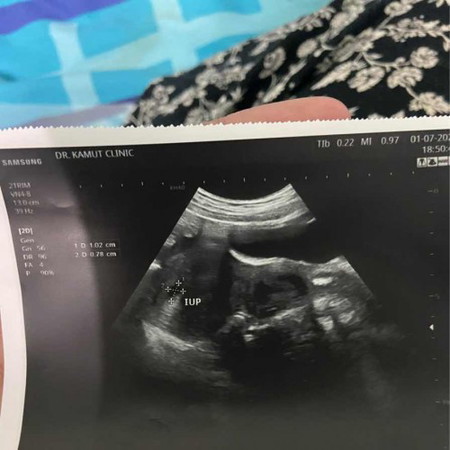

ช่วยดูภาพอัลตราซาวด์ให้หน่อยค่ะแม่ๆบ้านไหนตอนท้องอ่อนเป็นแบบนี้บ้างคะประจำเดือนขาด6วันก็เลยไปตรวจหมอบอกยังไม่มีหัวใจน้องแบบนี้แปลว่าท้องลมมั้ยคะหรือยังไง😓หมอนัดอีกทีวันที่22ค่ะ

ท้องลม คือท้องที่ไม่ตัวอ่อน ถ้าอัลตราซาวด์จะเจอแค่ถุงตั้งครรภ์แต่ไม่เจอตัวอ่อน ท้องลมก็มีฮอร์โมน HCGขึ้นค่ะ ตรวจก็จะเจอ2ขีด แต่หลังจากนั้นถ้าไม่มีตัวเด็กก็จะฝ่อไปค่ะ ถ้าไม่ฝ่อเองก็จะต้องเหน็บยาให้ออกหรือขูดมดลูก ในกรณีที่ซาวนด์แล้วไม่เจอตัวเด็ก คุณหมออาจจะนัดมาซาวนด์ซ้ำเพื่อความแน่ใจ บางคนเห็นตัวเด็กช้าก็มีขอให้โชคดีนะคะ